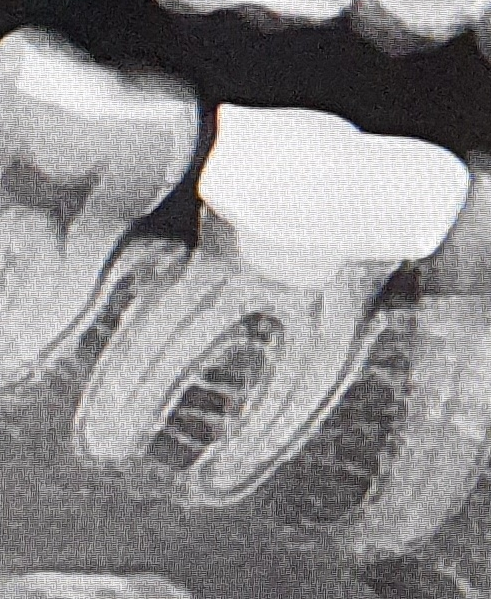

(크라운 벗겼을때 치아상태B병원 촬영)

문제는 이쪽이빨이 좀 많이썩어있었고 B병원에서 치료당시에 아이고 이빨이남아있는게 없네 라고하셨거든요

C병원에서도 제 크라운 벗겼을때 상태를모르니 그냥 신경치료 재치료하자 라고하신거라고생각이들어서요..

의사선생님들이 보기엔 이렇게 사진만봤을때 재치료가 가능해보이나요?

신경치료를 다시 하셔서 기둥세우고 크라운 치료를 하실수 있을것같습니다. 치료를 받으시는게 좋을것같습니다.

개인적인 소견으로는 살리기 힘들어 보이기는 합니다. 그래도 신경치료를 해서 살리자고 했으니 최대한 치료를 해보시는게 좋겠습니다.